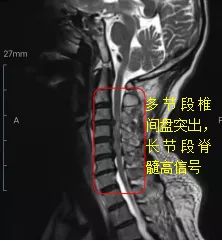

我院骨科主治医师胡萌接管病人后,结合病情及影像检查结果,考虑患者的瘫痪症状是因为颈脊髓损伤所致。“对于颈脊髓损伤的患者,我们脊柱专业组已有太多的诊治经验及成功案例,这类患者既往多存在颈椎间盘突出、韧带骨化、颈椎管狭窄等基础病情,在颈部遭受外力后,因颈段的脊髓没有太多的退让空间,出现脊髓损伤。但这一次我们面临了前所未有的挑战,因为患者不仅仅是局部的颈脊髓损伤,而是涉及多节段的椎间盘突出压迫脊髓,并出现了长节段的脊髓损伤信号改变”(如图1)。胡萌医生向患者坦言。“这是我们遇到的最复杂的一个情况”。

图1.术前颈椎磁共振